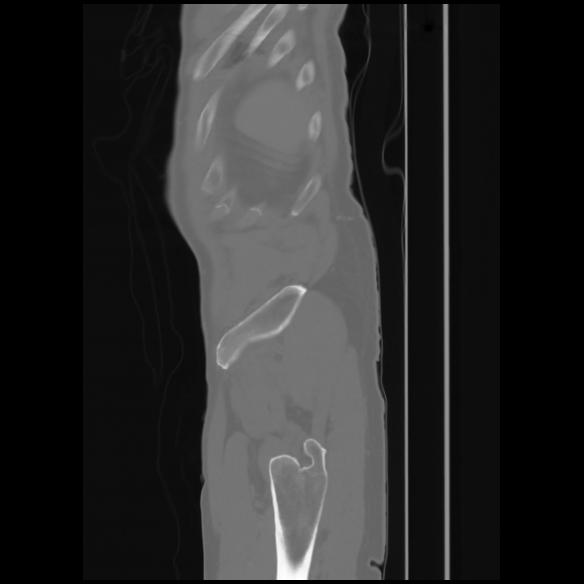

7 CUERPO,CE,Sagittal,3.000,CUERPO,Sagittal,